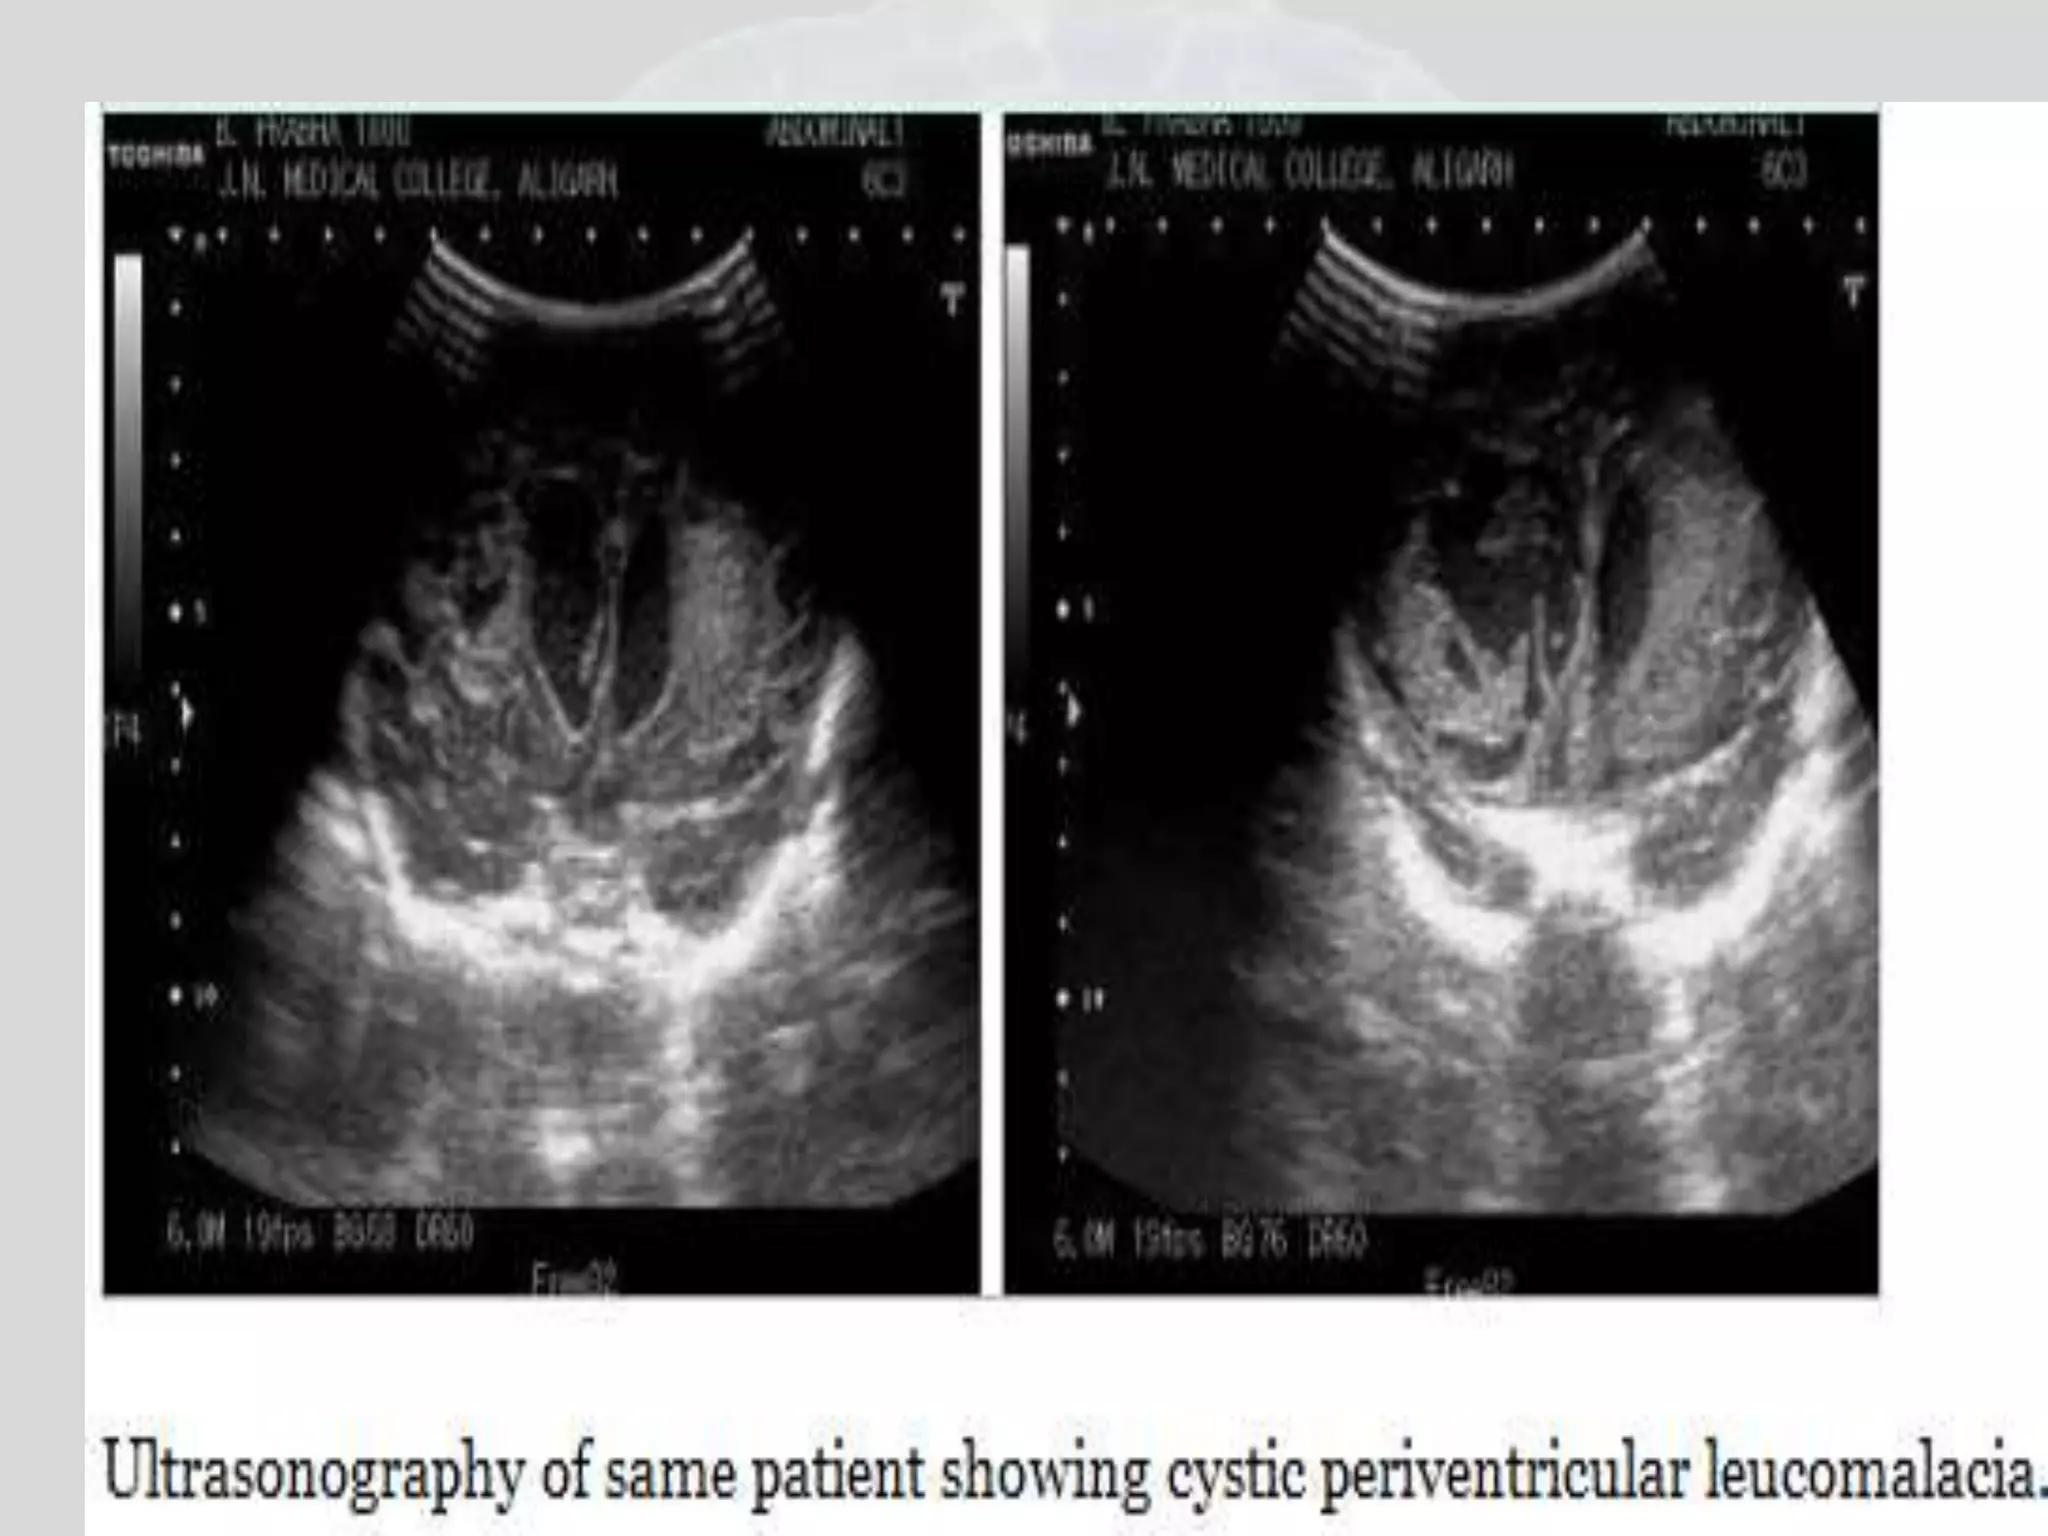

Early periventricular

leucomalacia:ultrasonography shows increased

echogenicity in B/L frontal and left parietal

region

Early periventricular leucomalacia:ultrasonographyshows increased echogenicity in B/L frontal and left parietal region